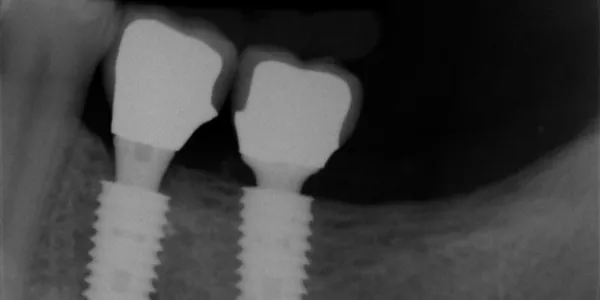

负重期的 X 光片,显示了两颗种植体在牙槽嵴下的植入差异。©Sergio Salina 博士

最近,《国际口腔种植学杂志》(International Journal of Oral Implantology) 上发表了一项随机、对照、多中心 3 年负重后研究的结果。这项研究的目的是评估在愈合的牙槽嵴下植入 0.5 mm 或 1.5 mm 的种植体是否会影响长期美学和生物学效果。

2013 年至 2018 年之间,在意大利的六个研究中心招募了 60 名局部无牙颌患者,他们需要植入两颗种植体支持式单冠修复体。两颗种植体被随机植入牙槽嵴下 0.5 mm 或 1.5 mm 处。

两种手术方案均产生了极佳的美学效果 (PES>12),并且 3 年后的骨吸收极少 (<0.5 mm)。与 0.5 mm 处相比,牙槽嵴下 1.5 mm 处植入时骨吸收略低,而对美学评分没有任何影响。这往往表明,种植体植入较深对保证骨稳定性有利,这将通过为期 5 年的随访来证实。